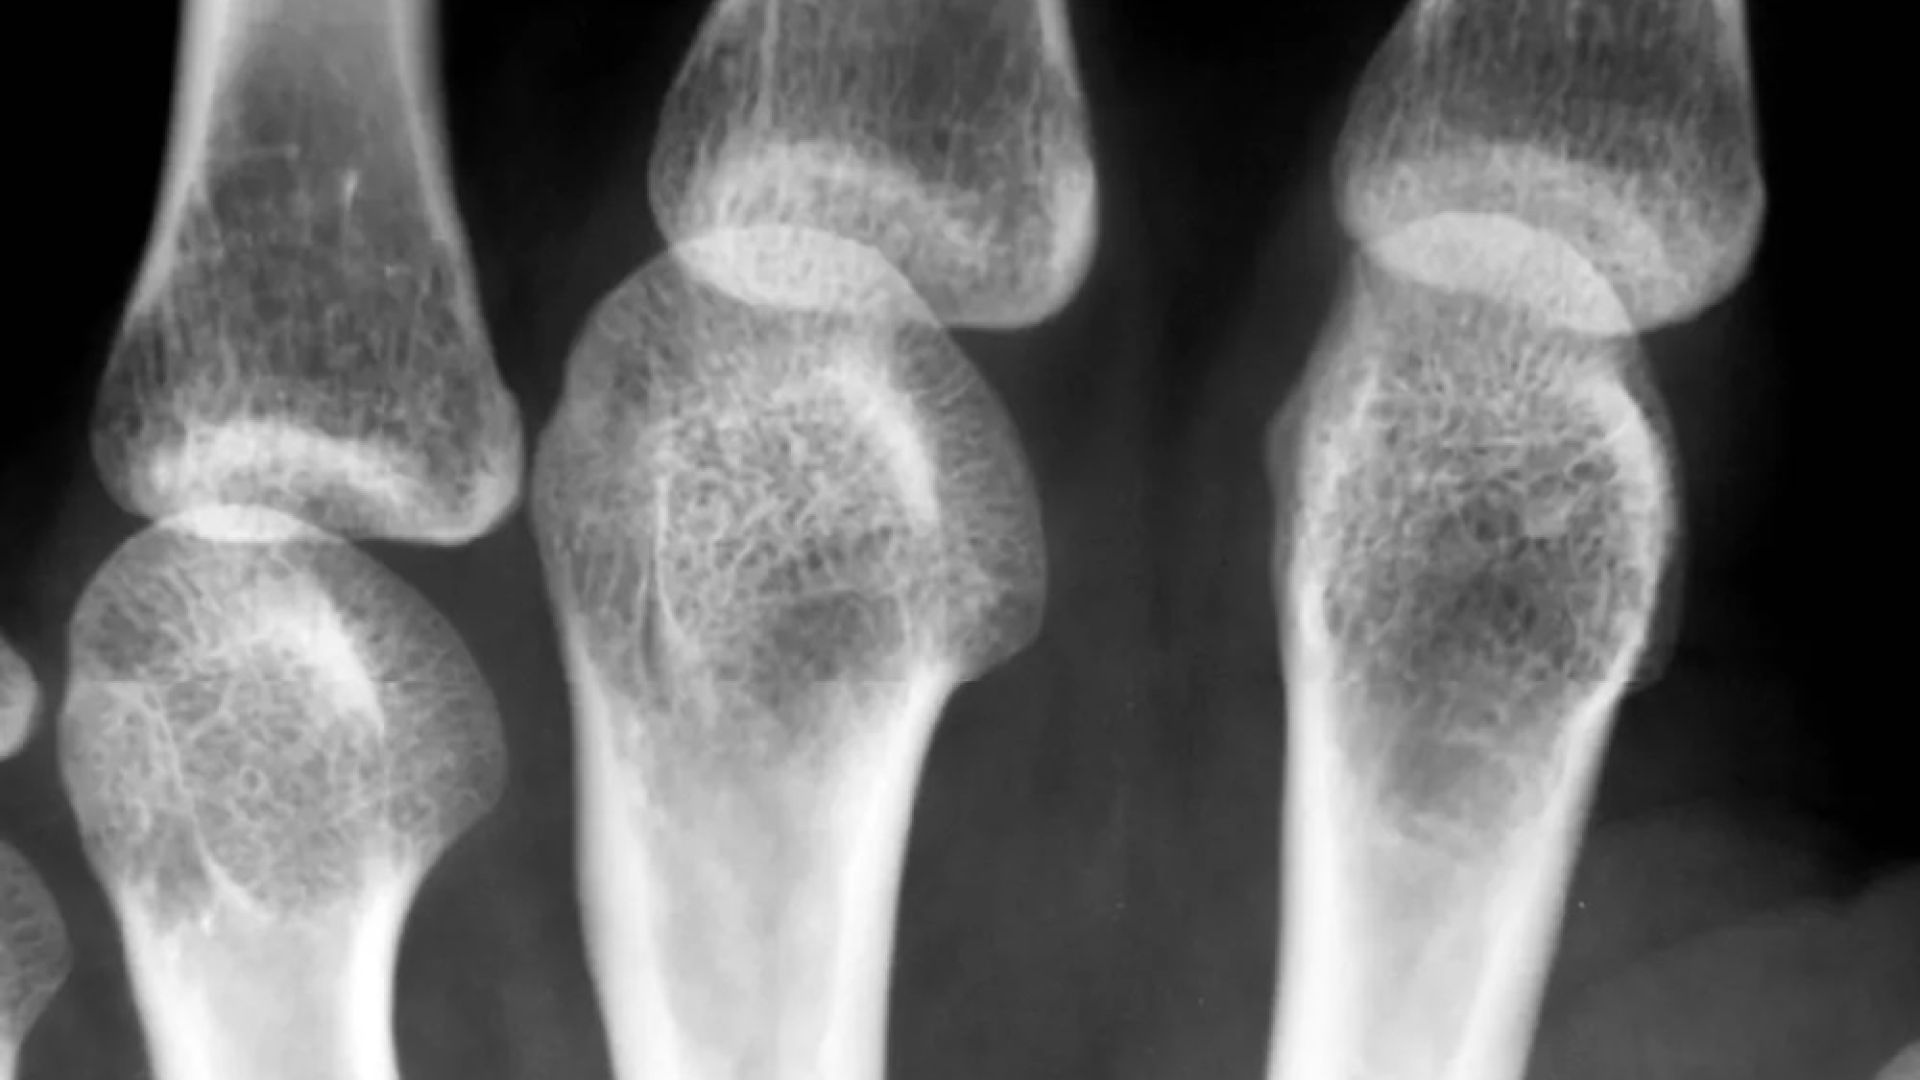

Лечение остеопороза

ПОКАЗАНИЯ: Остеопороз

• ультразвуковая денситометрия